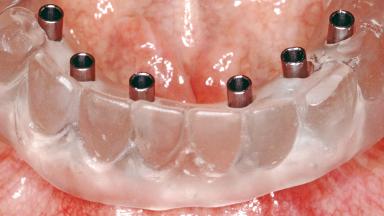

Conventional Loading of Six Implants in the Mandible and Final Restoration with a Full-Arch Metal-Ceramic FDP

A 68-year-old, completely edentulous male patient presented for evaluation and treatment options. He reported excellent general health and was taking no regular medication. He had been edentulous for approximately 12 years, having lost his teeth to periodontal disease and dental caries. The patient’s chief complaint was incompetent function. His secondary concerns included his appearance and the desire for a predictable outcome. He attributed his reduced functional capacity to his lower complete denture, which he described as poor. He was particularly concerned with the denture’s instability and poor fit. In general terms, he was satisfied with the maxillary complete prosthesis. The maxillary prosthesis was characterized by adequate retention, stability, and support, although the fit was considered less than ideal.